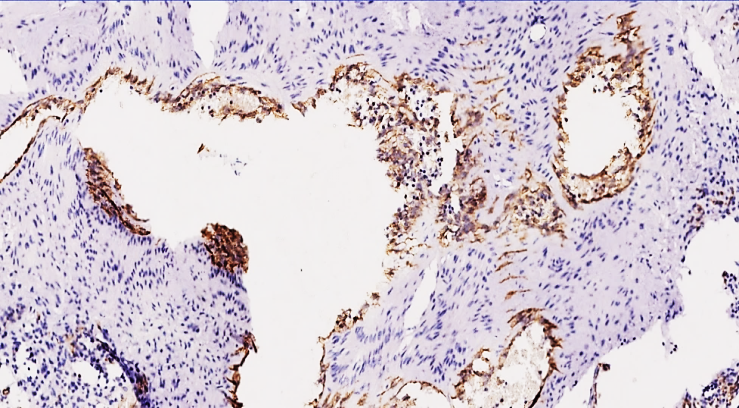

This confirms the low rate of damage to the lower vessels after the pulmonary veins were sutured with a thrombus or embolus in the postoperative period, as mentioned in the morphological studies.Our group 3, in the postoperative period in 60-74 year olds, the development of hypercoagulable syndrome mainly proceeds with the predominance of the thrombogenesis process in the vessels, and in clinical morphological terms, the increase in the biological tolerance index of the vessels, the fragility of the vessels and the very low content of the glycoprotein adsorbing protein component confirm the very low rate of angiogenesis and vascular damage. Biological aging of the vessels in 60-74 year olds and the absence of the adhesive glycoprotein that connects the endothelial cells to each other also mean that the endothelium responds very poorly to any influences. Of the 26 cases in group 3, 5 had low positive expression, while 21 had a predominance of negative reaction. Those that gave a positive reaction were mainly detected in tissues from the primary lung branch to the front, and were almost not detected in the 2nd and 3rd lung branches.Our next marker, CD 63, is also a membrane adhesive protein belonging to the tetraspanin family, and is a glycoprotein. The functional characteristics of this protein are characterized by staining Weibel-Palade bodies, which are mainly present in the blood and endothelial cells of the blood vessel wall. These bodies are mainly found in the endothelial cells of all vessels and contain the von Willebrand factor and the P-selectin protein. This factor is mainly due to hypercoagulability indicators in blood coagulation, adhesion of platelets in the tissue to the vascular wall, and since P-selectin is detected only in active platelets, they are collectively called Weibel-Palade bodies. Normally, these bodies are expressed by a negative reaction to the CD 63 marker, which means that the vessels are at rest.Now, in the period after any surgical operation in the body, mainly within 3-5 days, prostaglandins and cytokines produced in damaged tissues have a damaging effect on the vascular walls, which also depends on the type of surgical operation, its invasiveness, trauma, etc., and if the operation occurs with an average of 500-700 ml of bleeding, this is manifested by a decrease in positive reactions of this factor. For example, in polytraumas, bleeding of more than 1.2 liters gives a negative reaction to the CD 63 marker, which is explained by a sharp decrease in platelets, endotheliosis, desquamation of endothelial cells, and collapse of the vascular lumen. In group 1 of our study, in terms of the expression of the CD 63 marker, this indicator was expressed in 21 out of 26 subjects aged 18-44 years, which was also reflected in the above-mentioned age-related vascular response and adhesion of platelets to the endothelial layer and the presence of Weibel-Palade bodies in the cytoplasm of endothelial cells. The presence of Weibel-Palade bodies in the form of golden yellow granular inclusions in endothelial cells, confirming the presence of von Willebrand factor and P-selectin protein, is also explained by the fact that in the thromboembolic complications that occur in the postoperative period, damage to the vascular intima and activation of blood coagulation factors are also found in the small-caliber vessels of the pulmonary arteries. This, in turn, reveals the main point of the process of migration of the transferred thrombi and thrombogenesis. | Figure 5. 41-year-old 4 days after surgery. High positive expression of the SD 63 marker is determined mainly on the surface of the inner surface of the vessel endothelium and thromboblastin substrate. This also means that the vessel is damaged and the process of thrombogenesis is advanced. Paint Dab chromogenic. Size 4x10 |

| Figure 6. 44-year-old 5 days after surgery. High positive expression of SD 63 marker. On the surface of the vascular endothelium, platelet adhesion aggregation and sediments in the granular form of different sizes are determined. Aggregation of platelets preserved in thrombi formed in the vessel cavity is determined in granular form. Dab chromogen. The size is 20x10 |

Specifically, activation of Weibel-Palade bodies is manifested by the sequestration of leukocytes around the perimeter of thrombogenic foci, as a result of simultaneous activation of the P-selectin adhesive protein. | Figure 7. 42-year-old woman. 5 days after surgery. High positive expression of the CD63 marker. Adhesive aggregation of platelets in the form of plaques on the surface of the vascular endothelium and Weibel-Palade bodies in the cytoplasm of endothelial cells are detected. Staining is Dab chromogen. Size 20x10 |